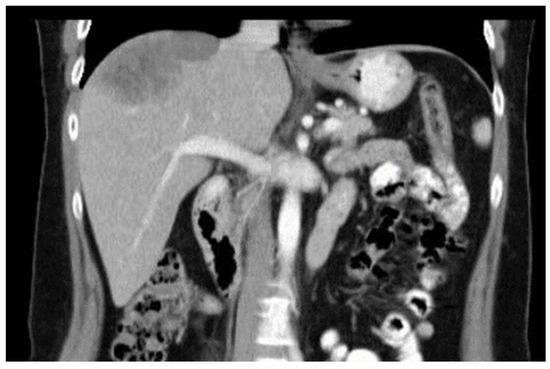

Diaphragmatic Liver Herniation after Radiofrequency Ablation of a Secondary Liver Tumor